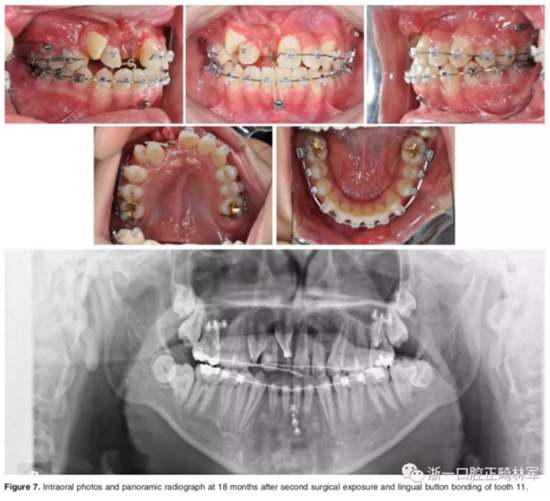

二期手術(shù)主要是牽引中切牙:于上頜前牙區(qū)腭側(cè)作切口,翻全厚瓣,在切牙唇側(cè)粘扣掛結(jié)扎絲牽引;軟組織愈合后,牽引開(kāi)始。為施加合適的垂直向力,在下頜前牙區(qū)放置C型管,掛橡皮筋牽引。14個(gè)月后,切牙牙冠萌出。使用mini管代替托槽,對(duì)切牙、尖牙進(jìn)行矯治;矯治過(guò)程采用輕力,0.014-in鎳鈦絲。

第三階段:

中切牙旋轉(zhuǎn)矯正后,患者至牙周科醫(yī)生處行右上前牙區(qū)骨增量手術(shù)。前牙區(qū)翻瓣后,使用Bio-oss及膠原膜覆蓋所有骨壁開(kāi)窗或較薄處,皮瓣復(fù)位縫合。2周后,繼續(xù)進(jìn)行正畸矯治。

影像學(xué):頭顱側(cè)位片示:矢狀向和垂直向骨骼發(fā)生變化(ANB角,3°;SN-MP,51°);上頜切牙略前傾(U1-SN,106°),與下頜切牙一致(IMPA,75°);病人的面部輪廓得以保持。全景片示:由于牙齒萌出,上前牙區(qū)垂直向牙槽骨水平增加;雖然前牙牙根較彎曲,但其平行度仍可,且無(wú)明顯的牙根吸收。CBCT示:前牙唇側(cè)骨質(zhì)連續(xù)性改善,牙根唇側(cè)支持組織變好,牙槽骨高度、厚度均有增加,但轉(zhuǎn)矩的改變一定程度上導(dǎo)致了局部應(yīng)力的增大。